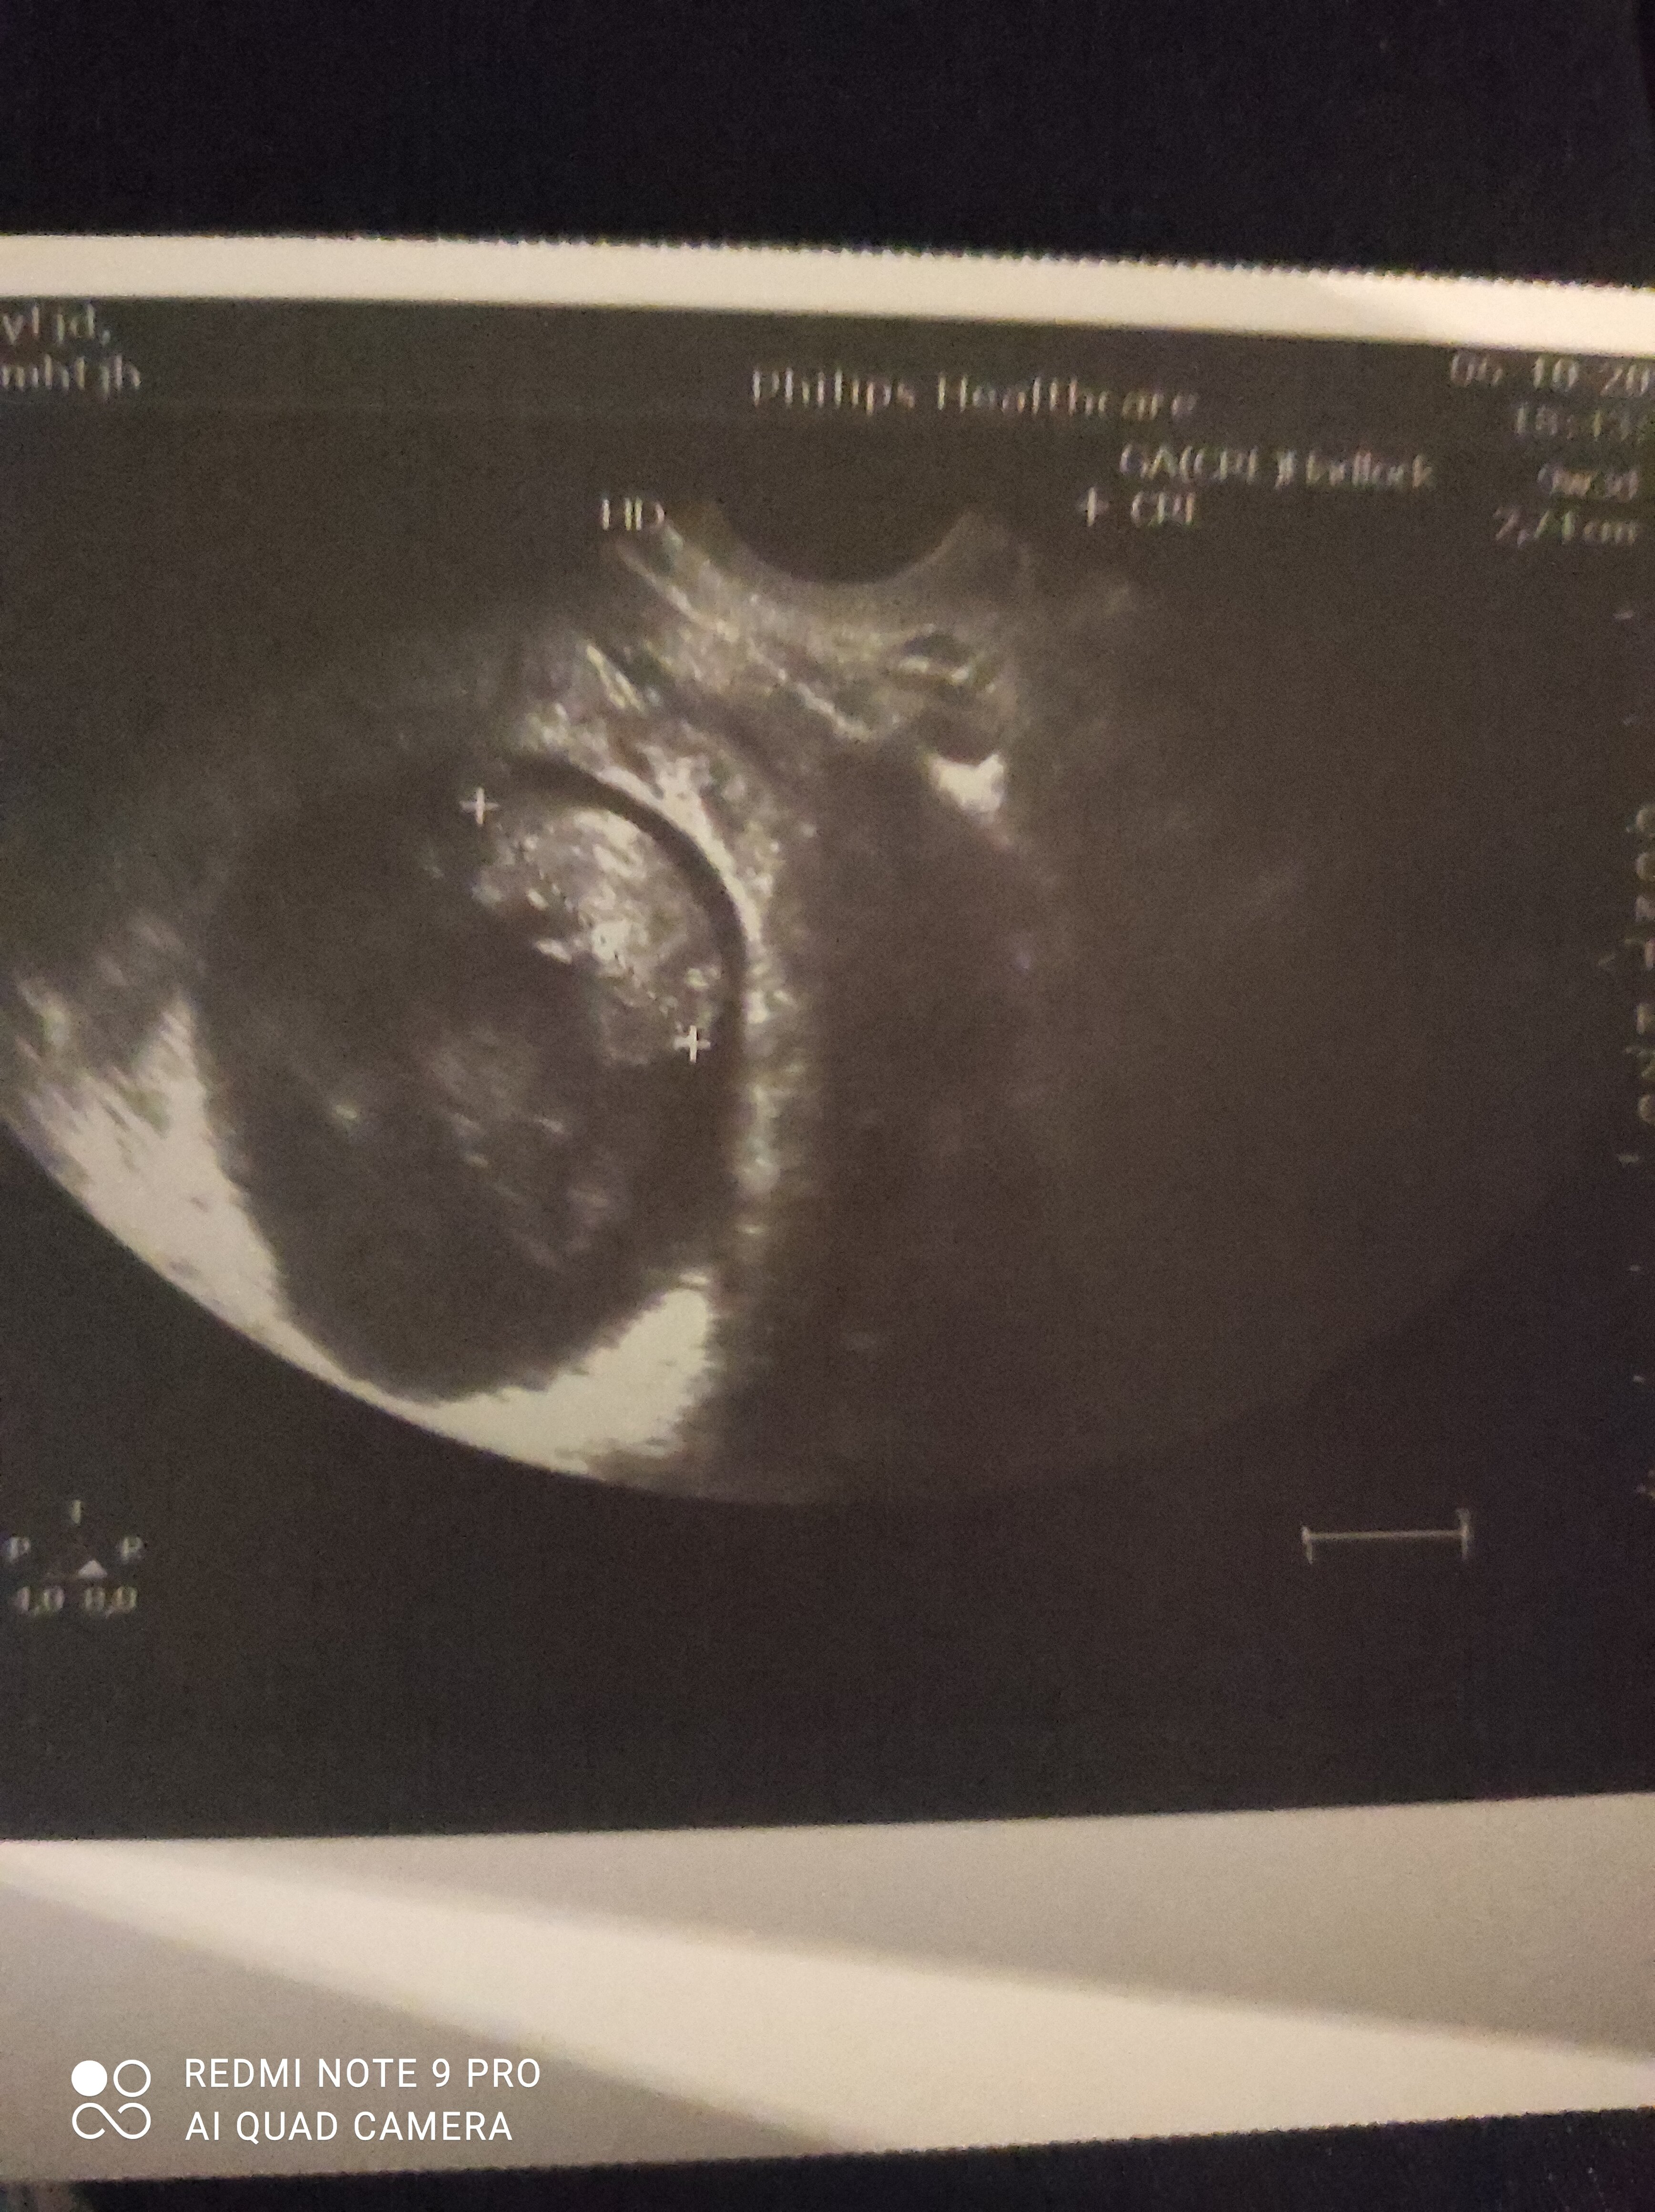

A ja wczoraj rozmawiając z lekarzem się tak wystraszyłam bo mam te ciała ketonowe w moczu a nie powinno ich być w ogóle i mi powiedział że one przez łożysko przechodzs i uszkadzają mózg dziecka a ja te badania i tak zrobiłam je dwa tygodnie później bo wcześniej lekarza nie było a nie wiem od kiedy je mam

i wyłam wczoraj wieczorem bo nie dość że zmiana w diecie dosyć drastyczną bo praktycznie nic nie mogę to jeszcze taka informacja a jeszcze czuje się przeziębiona a we wtorek mam wizytę USG na której mi mega zależy .. staram się wykurować